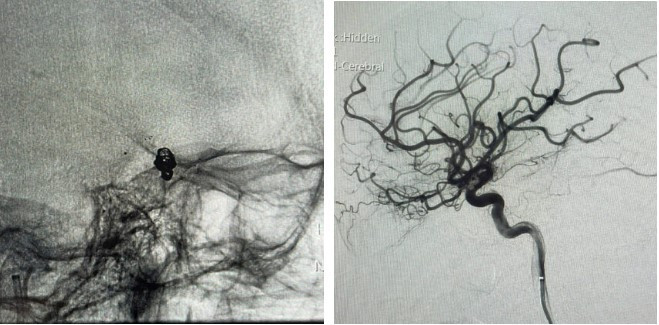

Ngay sau đó, bệnh nhân được chỉ định chụp DSA mạch não cấp cứu và tiến hành can thiệp nội mạch nút túi phình bằng coil, có hỗ trợ bằng stent nhằm loại bỏ nguy cơ chảy máu tái phát.

phinh-mach-1.png

Hình ảnh DSA mạch não trước can thiệp ghi nhận túi phình động mạch thông trước - Ảnh BVCC